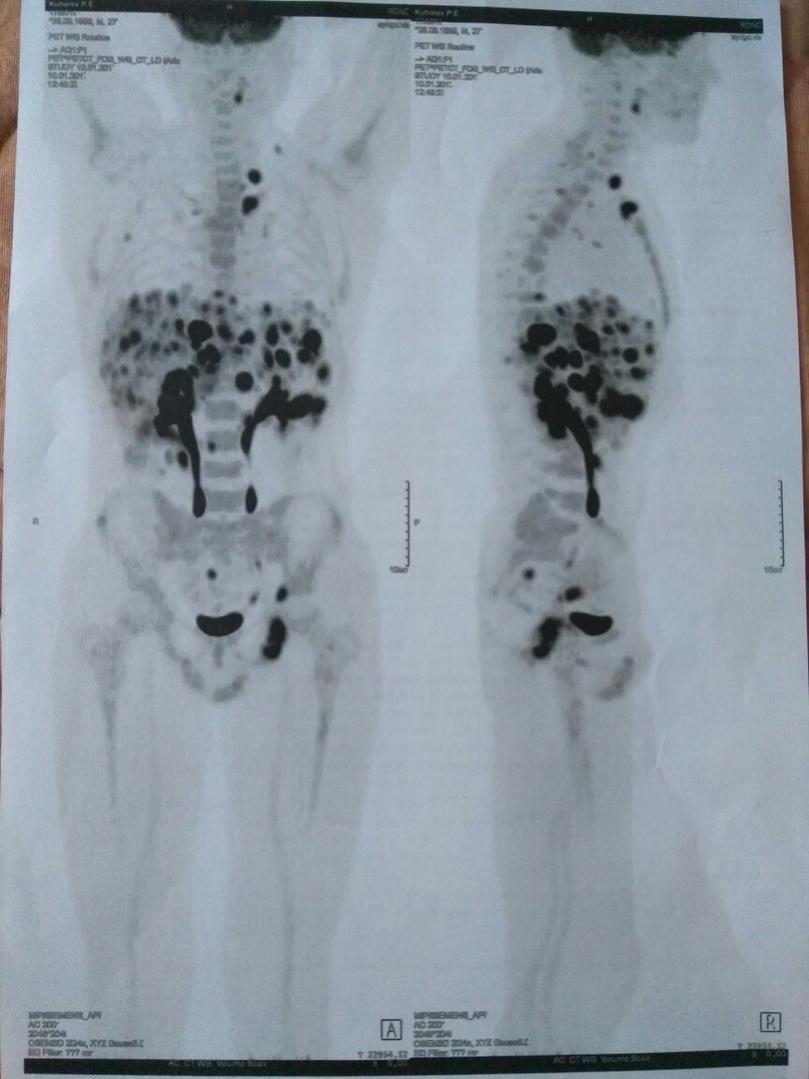

Преждевременная паника ни к чему. Делайте обследования и многое прояснится. ПЭТ КТ хорошо показывает накопление препарата в лимфоузлах.

Изображения

Тип файла: jpg BrE8u5Gk5go.jpg (67.7 Кб, 513 просмотров)